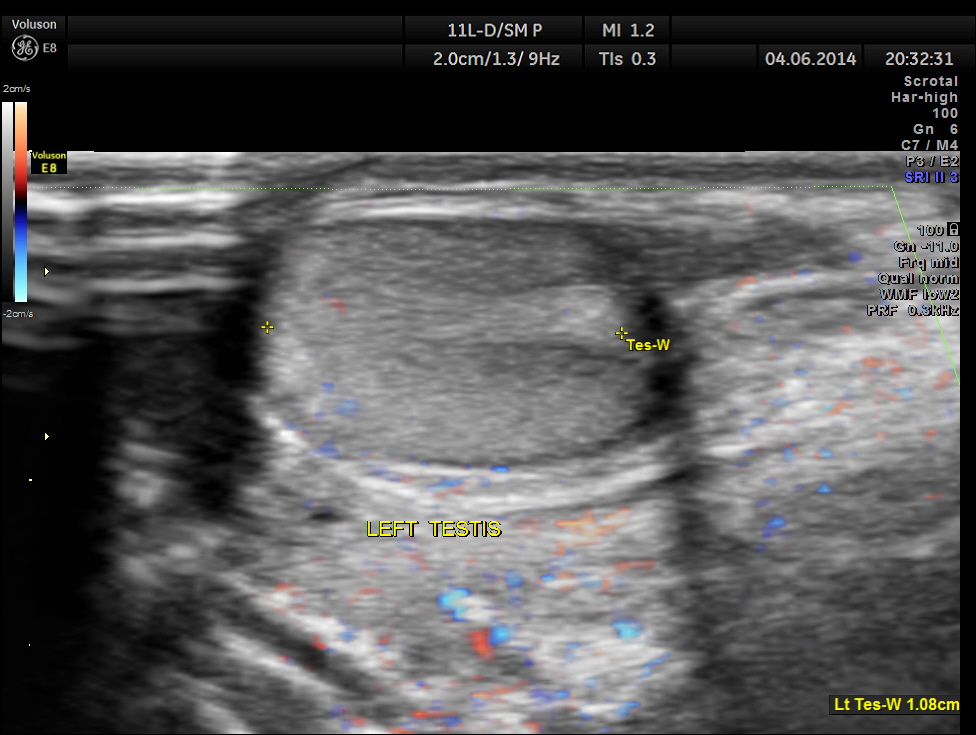

The images of the left testis are given below for comparison.

This was a case of acute epididymitis , without orchitis . In our part of the world filarial infestation leading to acute epididymitis is a common occurrence .